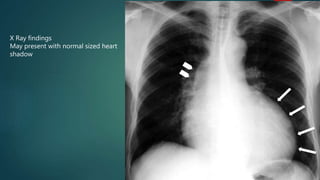

X Ray findings

May present with normal sized heart

shadow

Valve calcification

 On a lateral film the

presence of calcification

in the position of aortic

valve is a sign indicating

aortic stenosis.

• 32.

X Ray findings Maypresent with normal sized heart shadow

• 33.

Valve calcification  Ona lateral film the presence of calcification in the position of aortic valve is a sign indicating aortic stenosis.